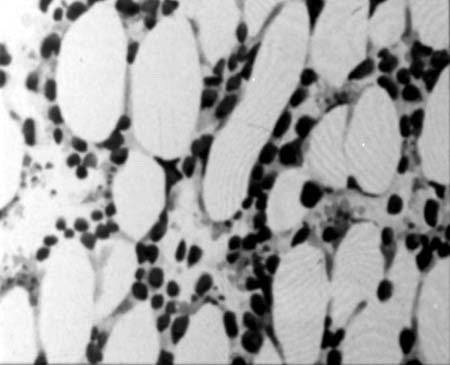

Гематологічні зміни характеризуються фазністю і відповідають ступеню радіаційного ураження. Фазність і послідовність змін складу елементів крові залежать від неоднакової радіочутливості, тривалості життя і термінів регенерації окремих кровотворних тканин. Найбільше уражаються лімфоцити й еритробласти. Відразу після опромінення у кістковомозковому кровотворенні спостерігають зниження мітотичної активності, зменшення молодих генерацій усіх клітин і відносне збільшення зрілих форм. Морфологічна картина кісткового мозку зазнає ряду фазових перетворень: спочатку переважають розпад і дегенерація елементів (рис.10.1), пізніше розвивається фаза гіпоплазії й аплазії, за нею — фаза інтенсивної регенерації.

Рис.1. Спустошення кісткового мозку.